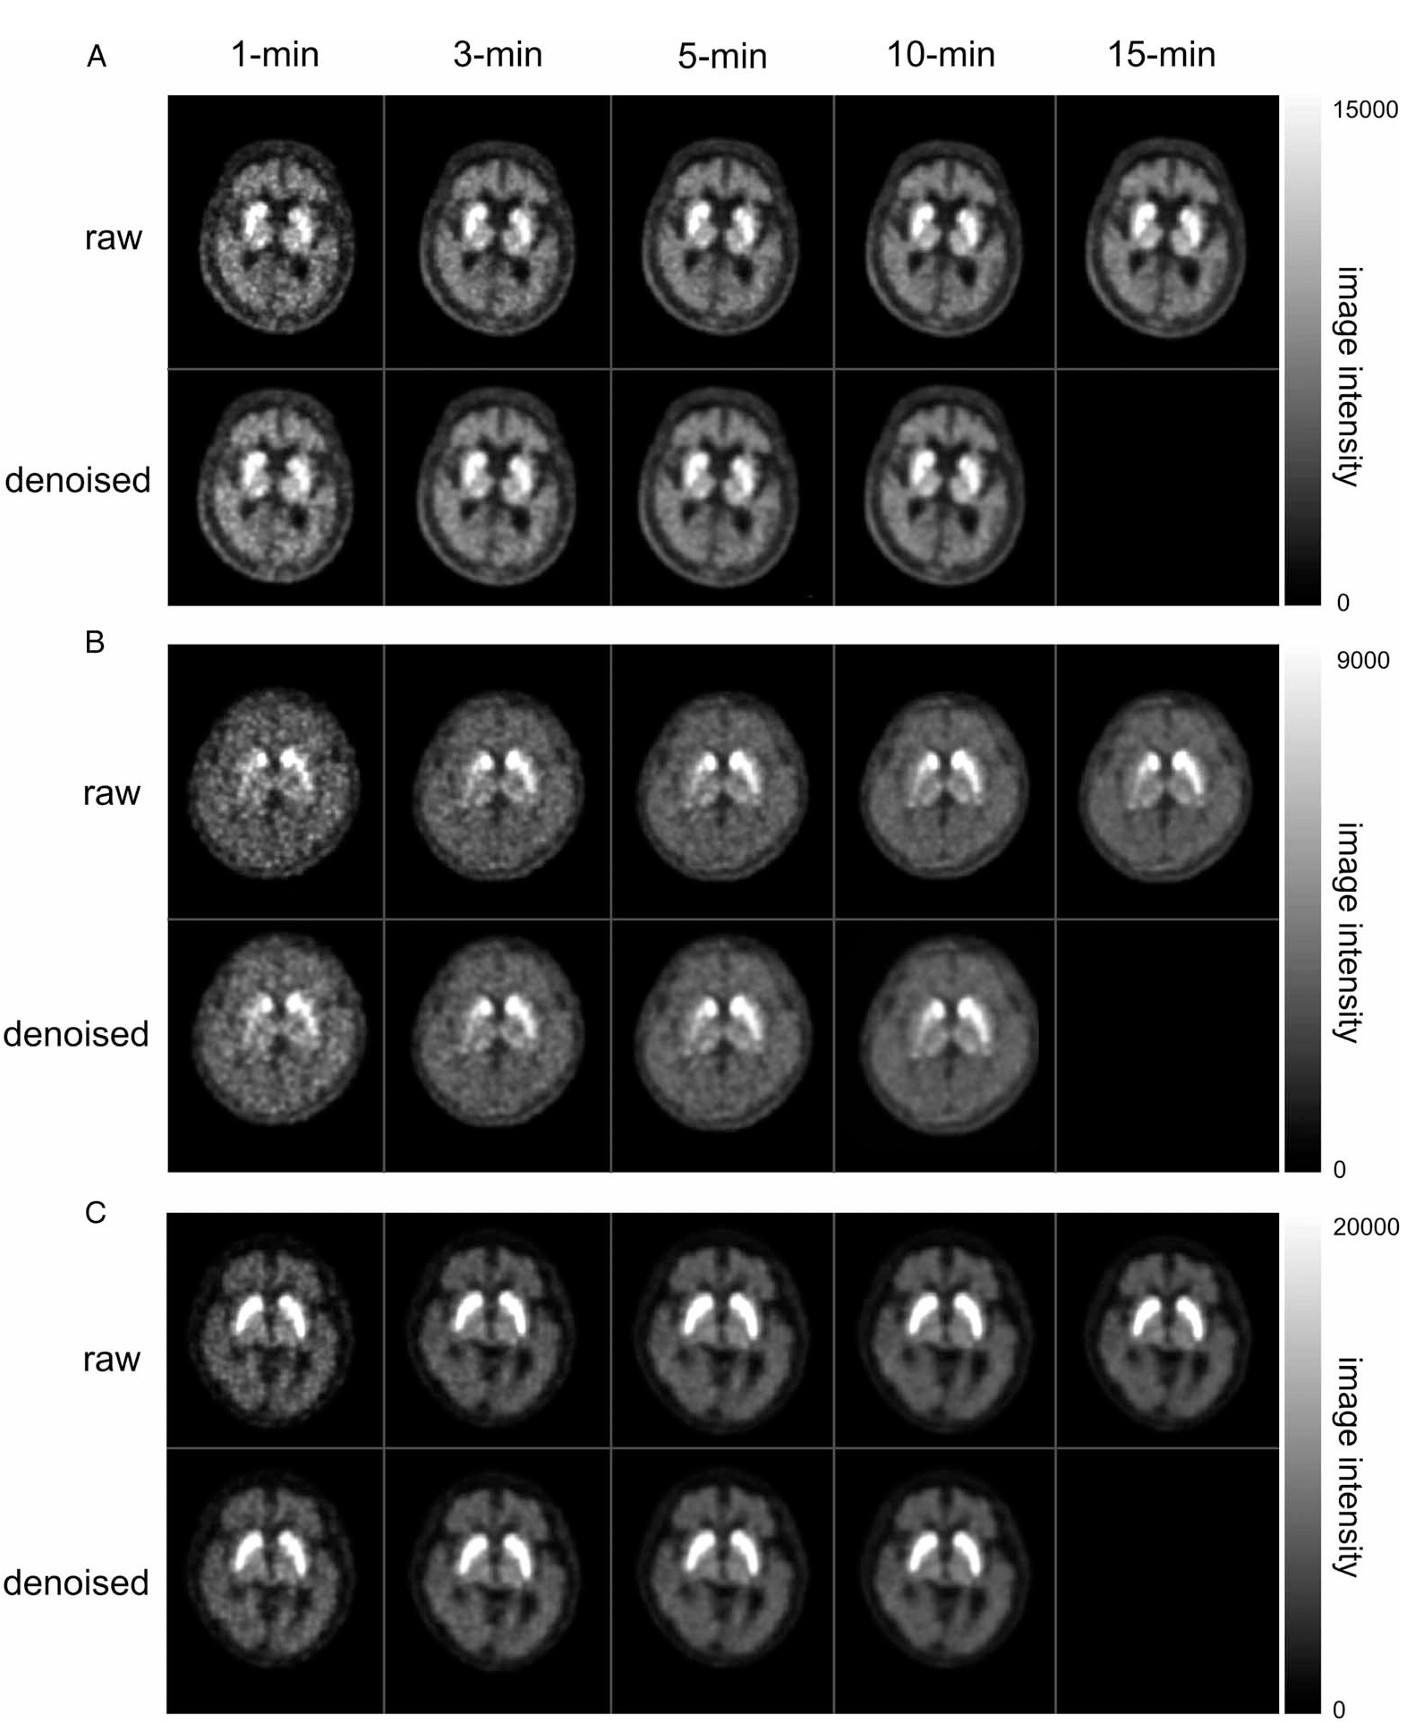

I have developed medical imaging solutions focused on PET and MRI analysis, including dose/time reduction for brain PET and AI-guided prostate lesion detection. I also contributed to automated diagnostic report generation and the regulatory approval of medical software devices (K-FDA).

[2025.07] "GAN-based Denoising for Scan Time Reduction and Motion Correction of 18F FP-CIT PET/CT: A Multicenter External Validation Study" was accepted to Clinical Nuclear Medicine (Impact Factor=10.0)!🎉

Hyunkyung Han, Kyobin Choo, Tae Joo Jeon, Sangwon Lee, Seungbeom Seo, Dongwoo Kim, Sun Jung Kim*, Suk Hyun Lee*, Mijin Yun*

Clinical Nuclear Medicine